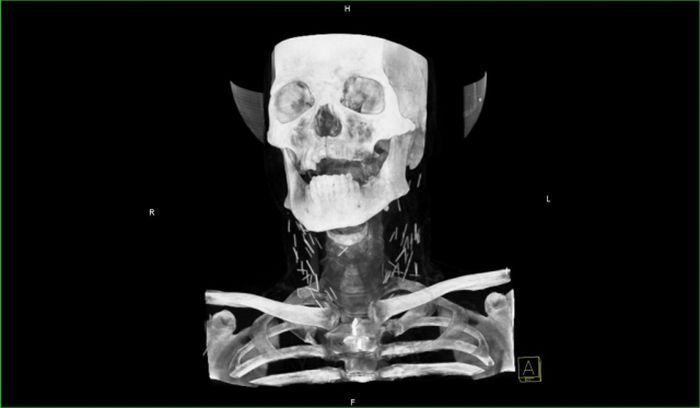

Рентген показал, что у чувака в шее огромное количество иголок.

Оказалось, что товарищ - нарк со стажем и все эти иглы остались в шее после неаккуратных инъекций.